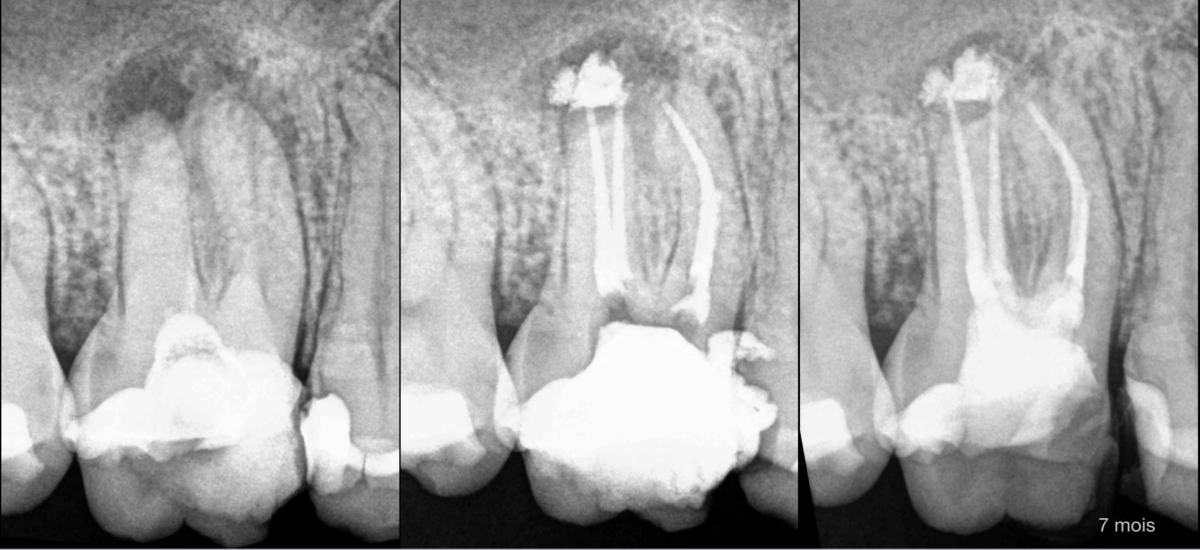

🗓️ À 7 mois : le traitement semble efficace du point de vue de la cicatrisation osseuse.

⚠️ Pourtant, la patiente nous signale de nouvelles douleurs… Pourquoi ?